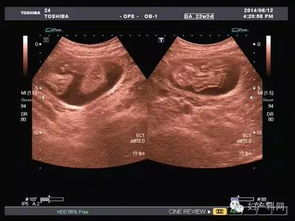

超聲波檢查,通過超聲波檢查出胎寶寶的體重、位置、大小。胎盤位置、羊水數(shù)量、呼吸運動等情況,以便判斷是進行自然分娩還是剖腹產(chǎn)

特別是對于月經(jīng)不準或者記不清楚最后一次月經(jīng)的孕媽媽來說,在懷孕早期可以利用超聲波檢查預見預產(chǎn)期。還可以檢查胎兒是否缺氧,或者孕婦是否是宮外孕。但是,超聲波最主要的還是堅持寶寶在腹中的生長情況。

現(xiàn)代社會,雖然科技在不斷發(fā)展,但是環(huán)境也在受到更嚴重的污染,這就導致了許多畸形胎兒的生長,而超聲波檢查就能告訴你胎兒生長是不是正常,是否有什么缺陷,有特別的情況的話,醫(yī)生通過超聲波檢查可以告訴你,比如,有些遺傳病可以在寶寶出生之前檢查出來,比如營養(yǎng)性肌肉發(fā)育不良,如果是男孩的話很容易造成遺傳,這樣的話醫(yī)生會通過檢查結果告訴你最好不要孩子。

一般來說,在第18周-20周進行第一次超聲波檢查。它能大致診斷出胎兒是否畸形,觀察胎兒的活動狀態(tài)。

在懷孕第34周第二次超聲波檢查的目的是監(jiān)測羊水量、胎盤位置、胎盤成熟度及胎兒有無畸形,了解胎兒發(fā)育與孕周是否相符。 最后是在第37周以后,超聲檢查主要目的是確定生產(chǎn)方式,為了監(jiān)測羊水量、胎盤成熟度,必要時需要每周一次B超。